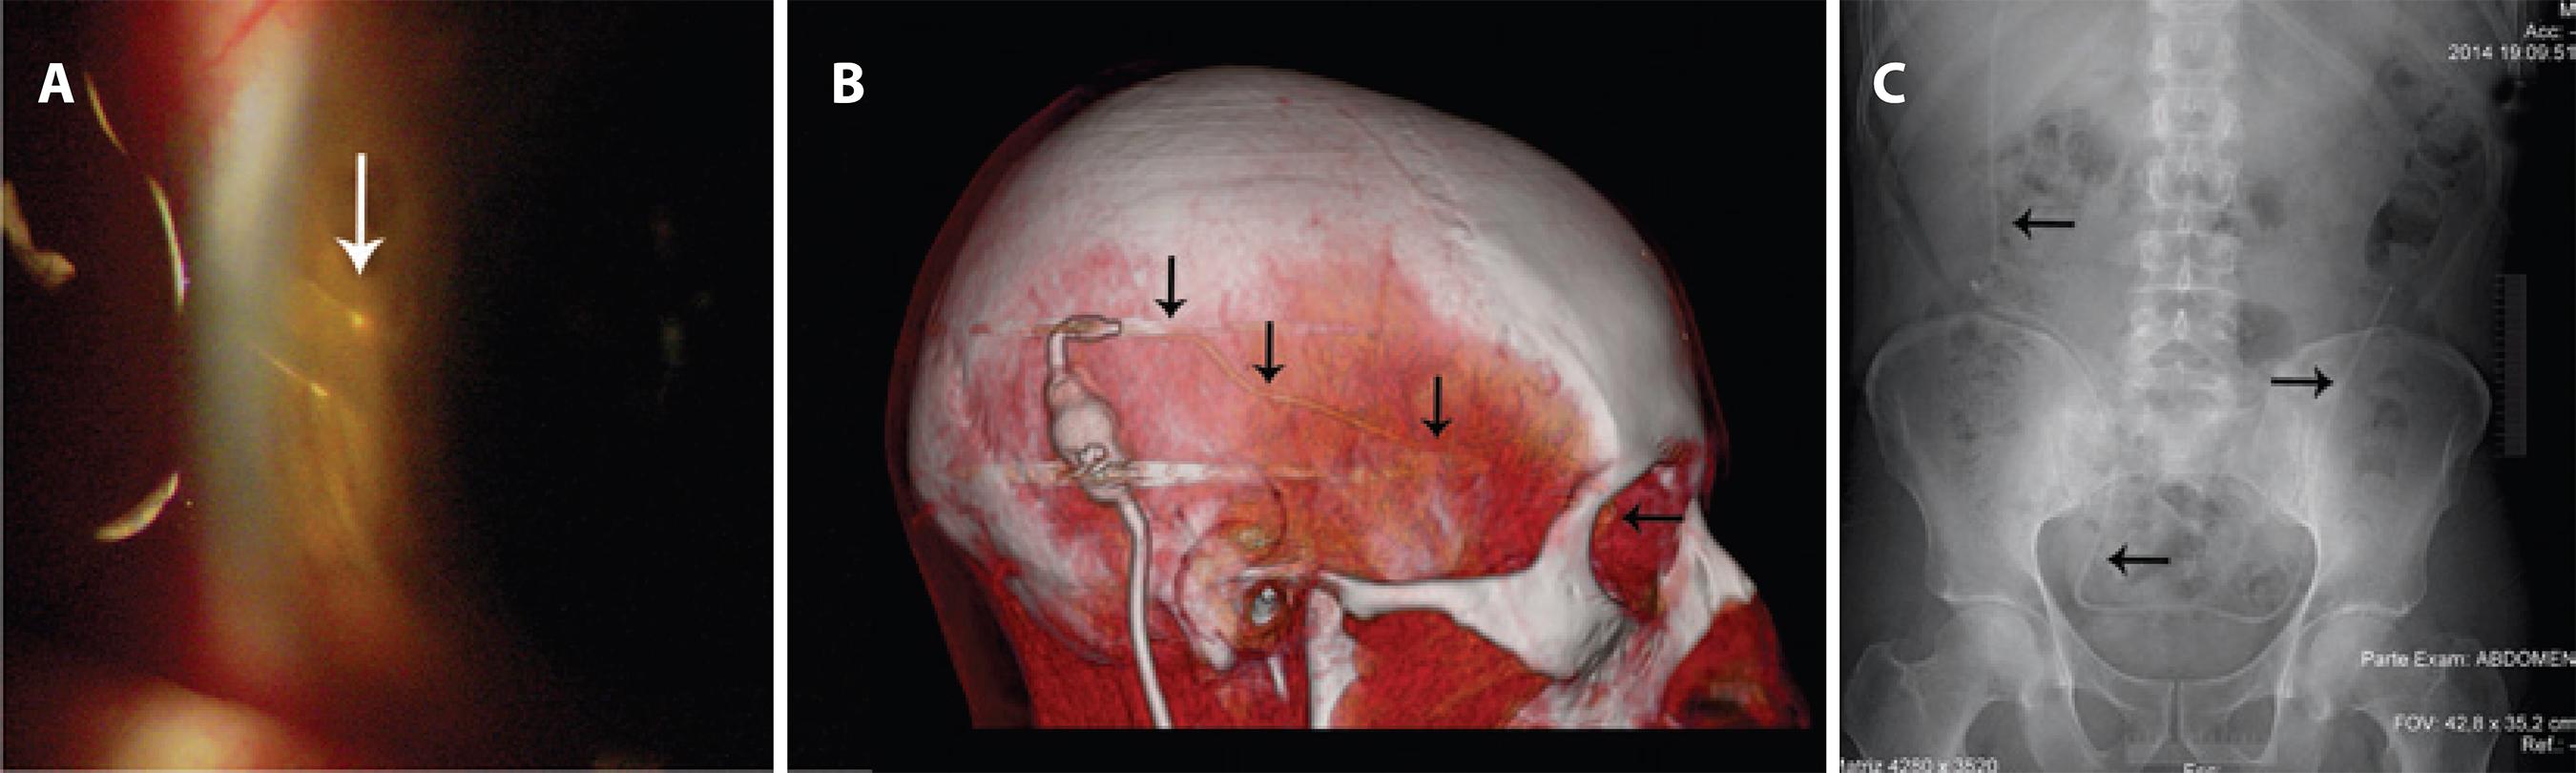

On slit-lamp examination, and in the tomographic and radiological investigations in the fourth week after surgery, the catheters and valve were confirmed to be well located. (Figures 4 A-C).

Figure 4 A) Slit-lamp examination showing the ocular catheter in position. B) Tomographic view showing the route of the ocular catheter (black arrows). C) Radiological view showing the peritoneal catheter in position (black arrows).